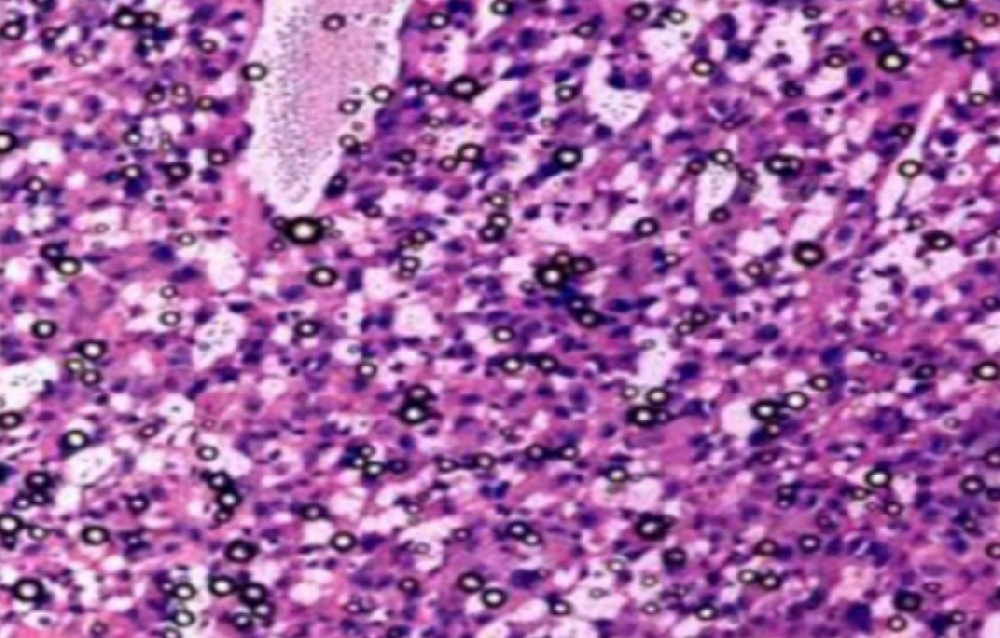

方法 使用清洁级的SD大鼠, 确定临产期,摘除*宫后,在隔离器内剥离大鼠幼崽,使用人工方法哺乳至22d离乳,记录体重和生存率。 使用的配方奶中,加入深度水解蛋白无乳糖奶粉的为实验组,对照组中加入全价配方奶粉。 对培育成功的无菌大鼠在第8周时检测血生化指标。

结果 在人工喂养的前14天,实验组与对照组在体重和生存率上都无差别,从第14天开始实验组的体重和生存率开始高于对照组,直至第22天实验组的生存率与对照组相比极显著提高(37.18% vs17.78%),第22天的体重也显著高于对照组(9.96±0.49)vs(13.36±0.59)。 无菌大鼠的血生化指标显示AST(天门冬氨酸氨基转移酶)降低,GLU(葡萄糖)升高。

结论 在培育无菌大鼠幼鼠阶段的过程中,深度水解蛋白的无乳糖奶粉可以作为配方奶成分的重要的成分进行添加,可以有效的增加幼鼠体重,减少死亡率。 雌性无菌大鼠的血生化指标变动较大。